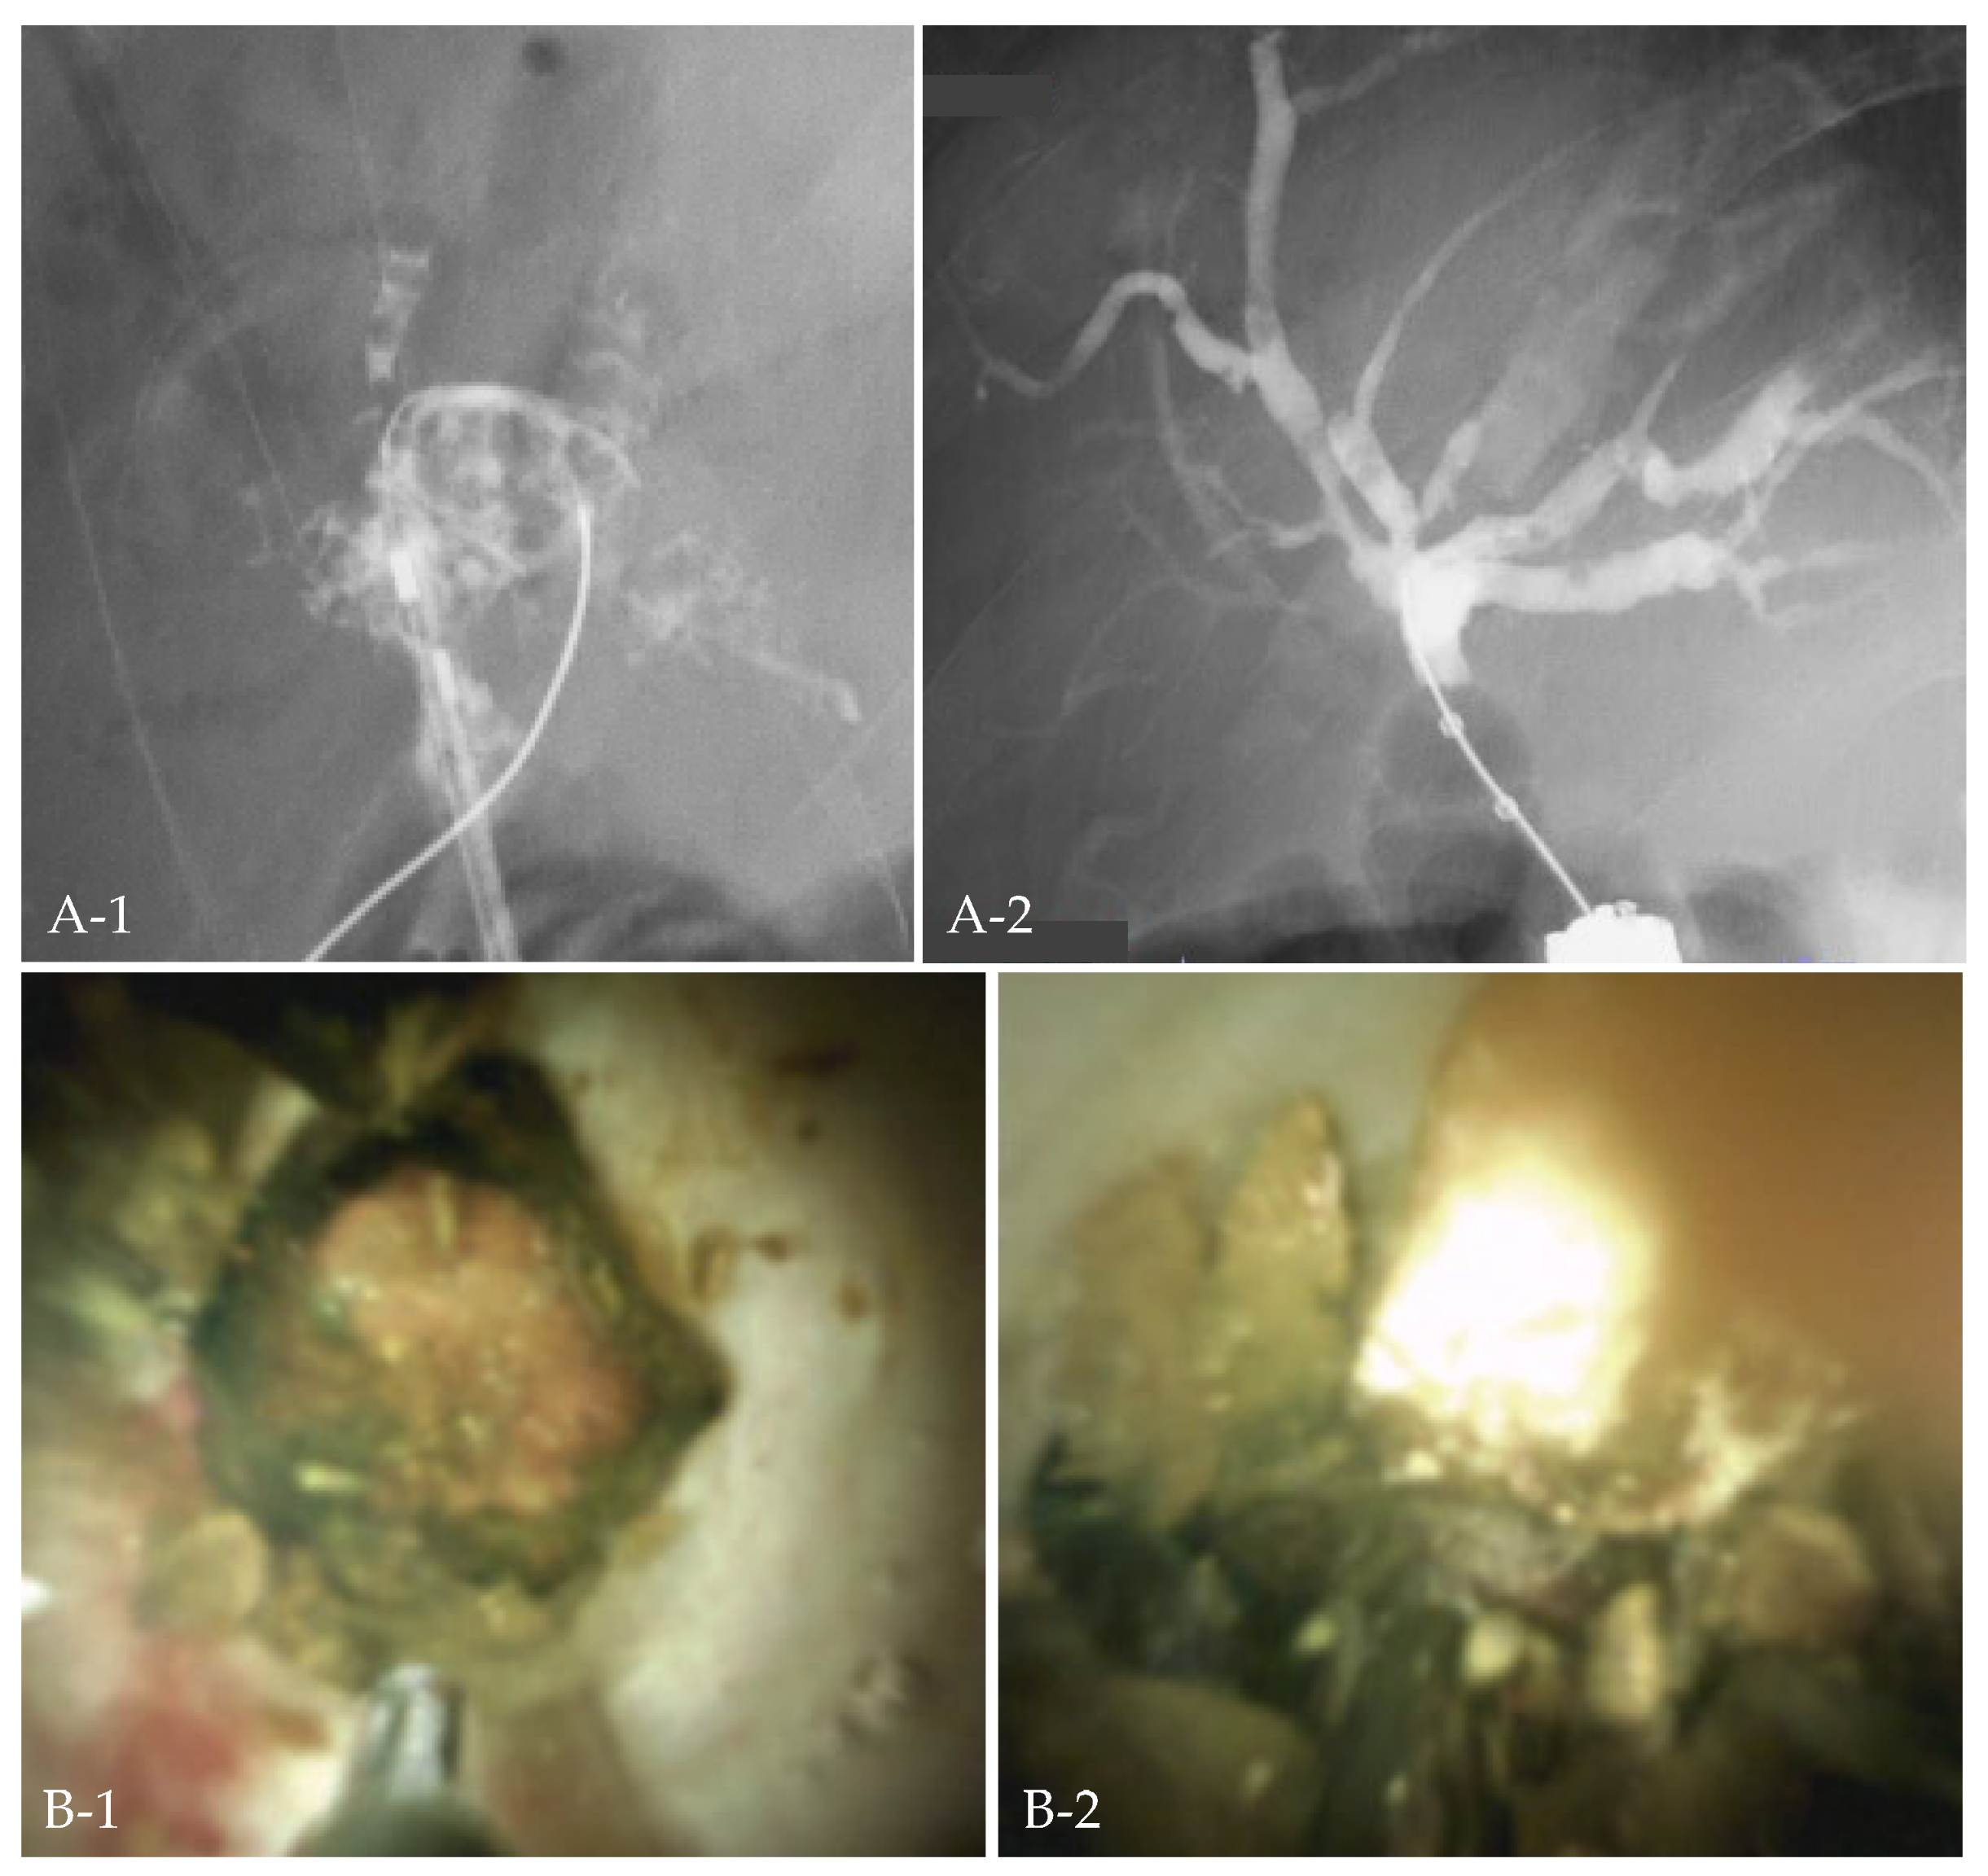

Figure 3.

Case 3. Cholangitis developed in a patient after pancreaticoduodenectomy, and the bile duct was filled with stones (A-1). Electrohydraulic shockwave lithotripsy under oral cholangioscopy with colonoscopy was performed (B-1,B-2), and all stones were removed (A-2).